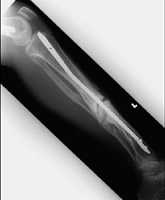

- Click on the image for a larger versionDLateral radiograph of the tibia and fibula. Notice the dense band of sclerosis at the fracture site. This appearance is due to nonunion of the fracture fragments.